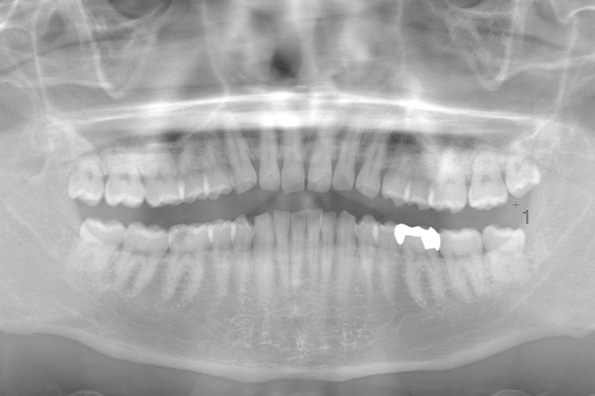

CASE 1

| 年齢・性別 | 30代・女性 |

|---|---|

| 主訴 | 左右に分けて親知らずを抜きたい、できれば痛くなく抜きたい |

| 親知らずのはえ方 | 完全に出ていてまっすぐはえている |

| 抜歯期間 | 15分 |

| 抜歯費用 | 約2,000円(保険内) |

| 抜歯内容 |

何度か虫歯になり痛みはないが早めに抜きたい。 完全に頭が出ているため歯ぐきを切ったり骨を削らずに抜歯しました。 根の形も単純なため抜歯自体は5分もかからず上下ともに終わりました。 術後痛みや腫れも出ていません。 抜歯後は感染をしやすいため必ず抗生物質を飲み切ってください。 |